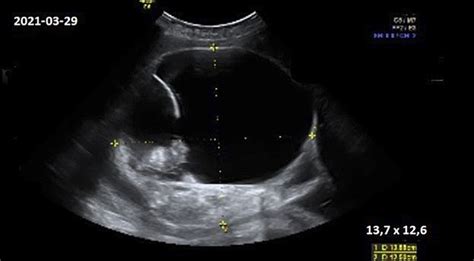

Oligohidramnionas diagnozuojamas, kai vaisiaus vandenų tūris sumažėja iki 500 ml ar mažiau trečiajame trimestre. Šis sutrikimas nustatomas ultragarsiniu tyrimu, vertinant vaisiaus vandenų indeksą, kuris tokiu atveju būna mažesnis nei 8 cm, o esant gerokai sumažėjusiam kiekiui - mažesnis nei 5 cm.

Diagnostika remiasi didesniu nei įprastai nėščiosios pilvu, įtempta gimda ir sunkiai apčiuopiamu vaisiumi. Pagrindinis tyrimas - ultragarsas, kurio metu nustatomas vaisiaus vandenų padidėjimo lygis. Pasekmės dažniausiai yra priešlaikinis gimdymas ir neišnešiotumas. Gimdymas gali būti sunkus dėl per silpnų gimdos susitraukimų. Valdymas apima ligoninėje atliekamus tyrimus priežastims nustatyti ir, prireikus, gimdymo sužadinimą, kurio metu gali būti pradurta vandenmaišio pūslė. Po gimdymo skiriami gimdą sutraukiantys vaistai kraujavimui užkirsti.

- Antrasis ir trečiasis trimestrai: Atliekama vaisiaus biometrija (BPD, FO, HC, ABD, AC, Fe), nustatomas nėštumo laikas, apskaičiuojamas vaisiaus svoris. Vertinama vaisiaus anatomija, placentos lokalizacija, storis, vaisiaus vandenų indeksas (AFI) ir tūris (AFV).

- Amniocentezė: Vandenmaišio punktavimas ultragarsu. Atliekama nuo 14-16 savaitės, siekiant nustatyti vaisiaus kariotipą, plaučių brandumą, aptikti infekcijas ir kt. Komplikacijų rizika yra nedidelė (0,5-1,0 proc.).